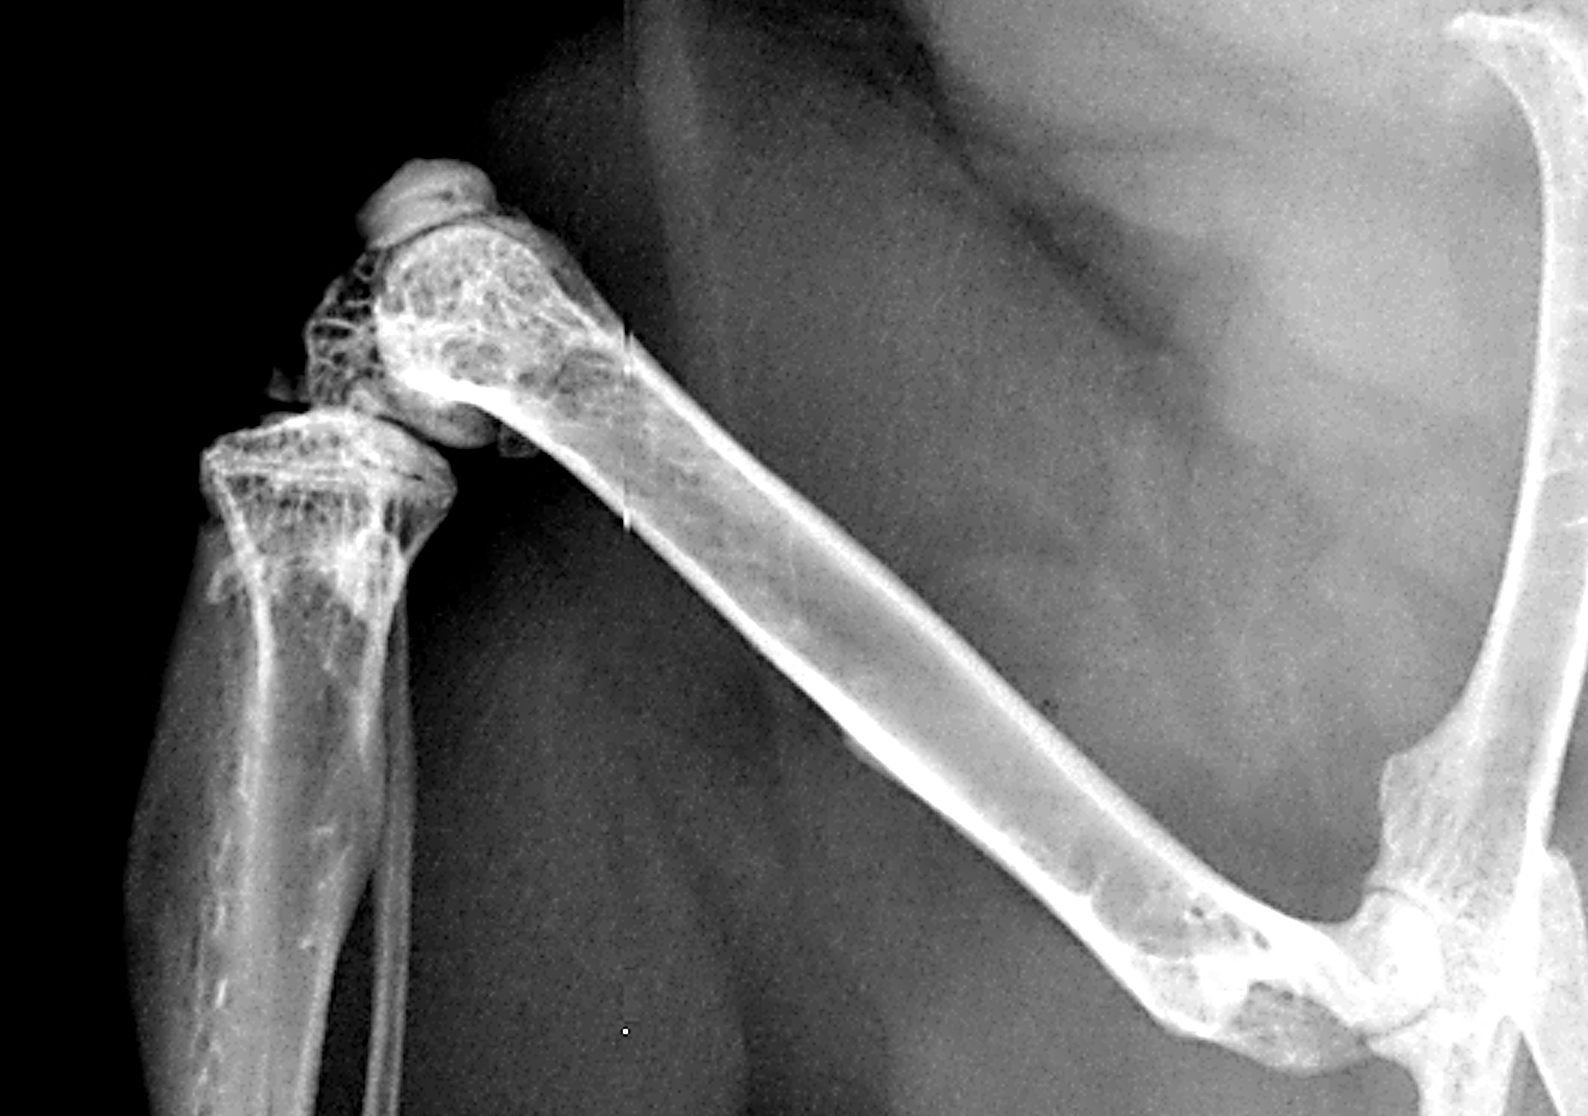

Chronischer Stress ist schlecht für gebrochene Knochen - Wie starke psychische Belastungen die Frakturheilung hemmen

Rettungskräfte im Notfall-Einsatz stehen massiv unter Stress, genauso wie Opfer von Naturkatastrophen und Gewalttaten. Im Falle einer schweren Verletzung bleibt dies nicht ohne Folgen. Denn mittlerweile gilt es als erwiesen, dass massive Stresserfahrungen und posttraumatische Belastungen die Wund- und Knochenheilung verzögern. Eine Studie der Ulmer Universitätsmedizin hat nun die molekularen Mechanismen identifiziert, über die psychische Traumen und andere massive Stresserfahrungen die Heilung von Knochenbrüchen verzögern.